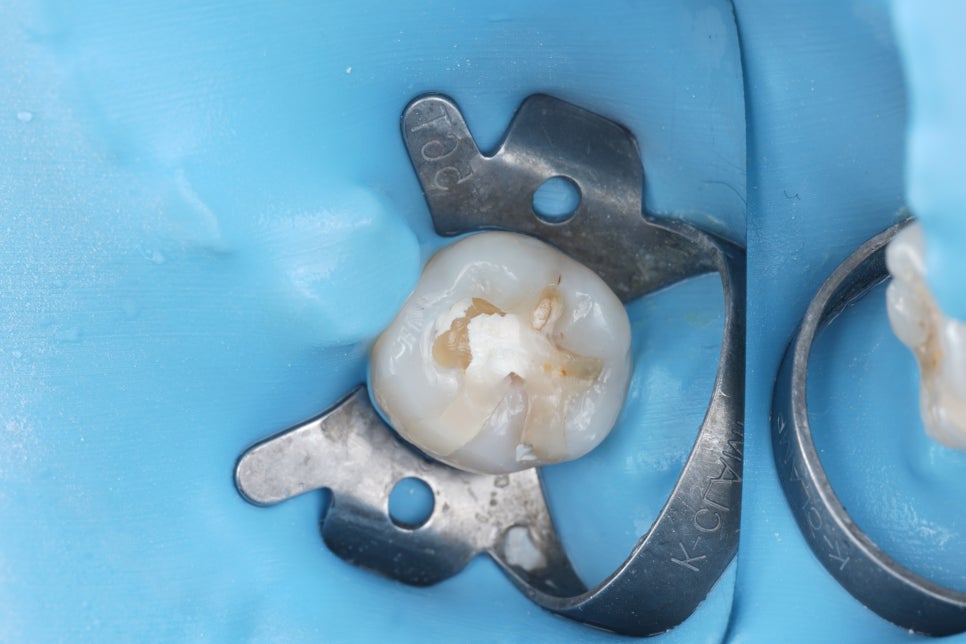

기존 재료 아래에 하얗게 굳은 재료(ZPC로 추정)가 두껍게 깔려 있었어요.

촬영일 : 251110

쉽게 말하면 레진이 치아에 붙어 있는 게 아니라 ‘시멘트 같은 재료’ 위에 붙어 있는 구조였던 거죠.

이 구조는 아무리 레진을 잘해도

깨지고 빠질 수밖에 없어요...

레진은 치아에 직접 붙어야 튼튼해지거든요.

그래서 저희는 기존에 했던 재료를 최대한 깨끗하게 걷어내고 바닥을 다시 정리했어요.

그리고 그 치아에 직접 레진이 단단하게 붙도록 구조를 다시 만들고 씹는 힘이 골고루 분산되도록 모양도 재설계했어요.